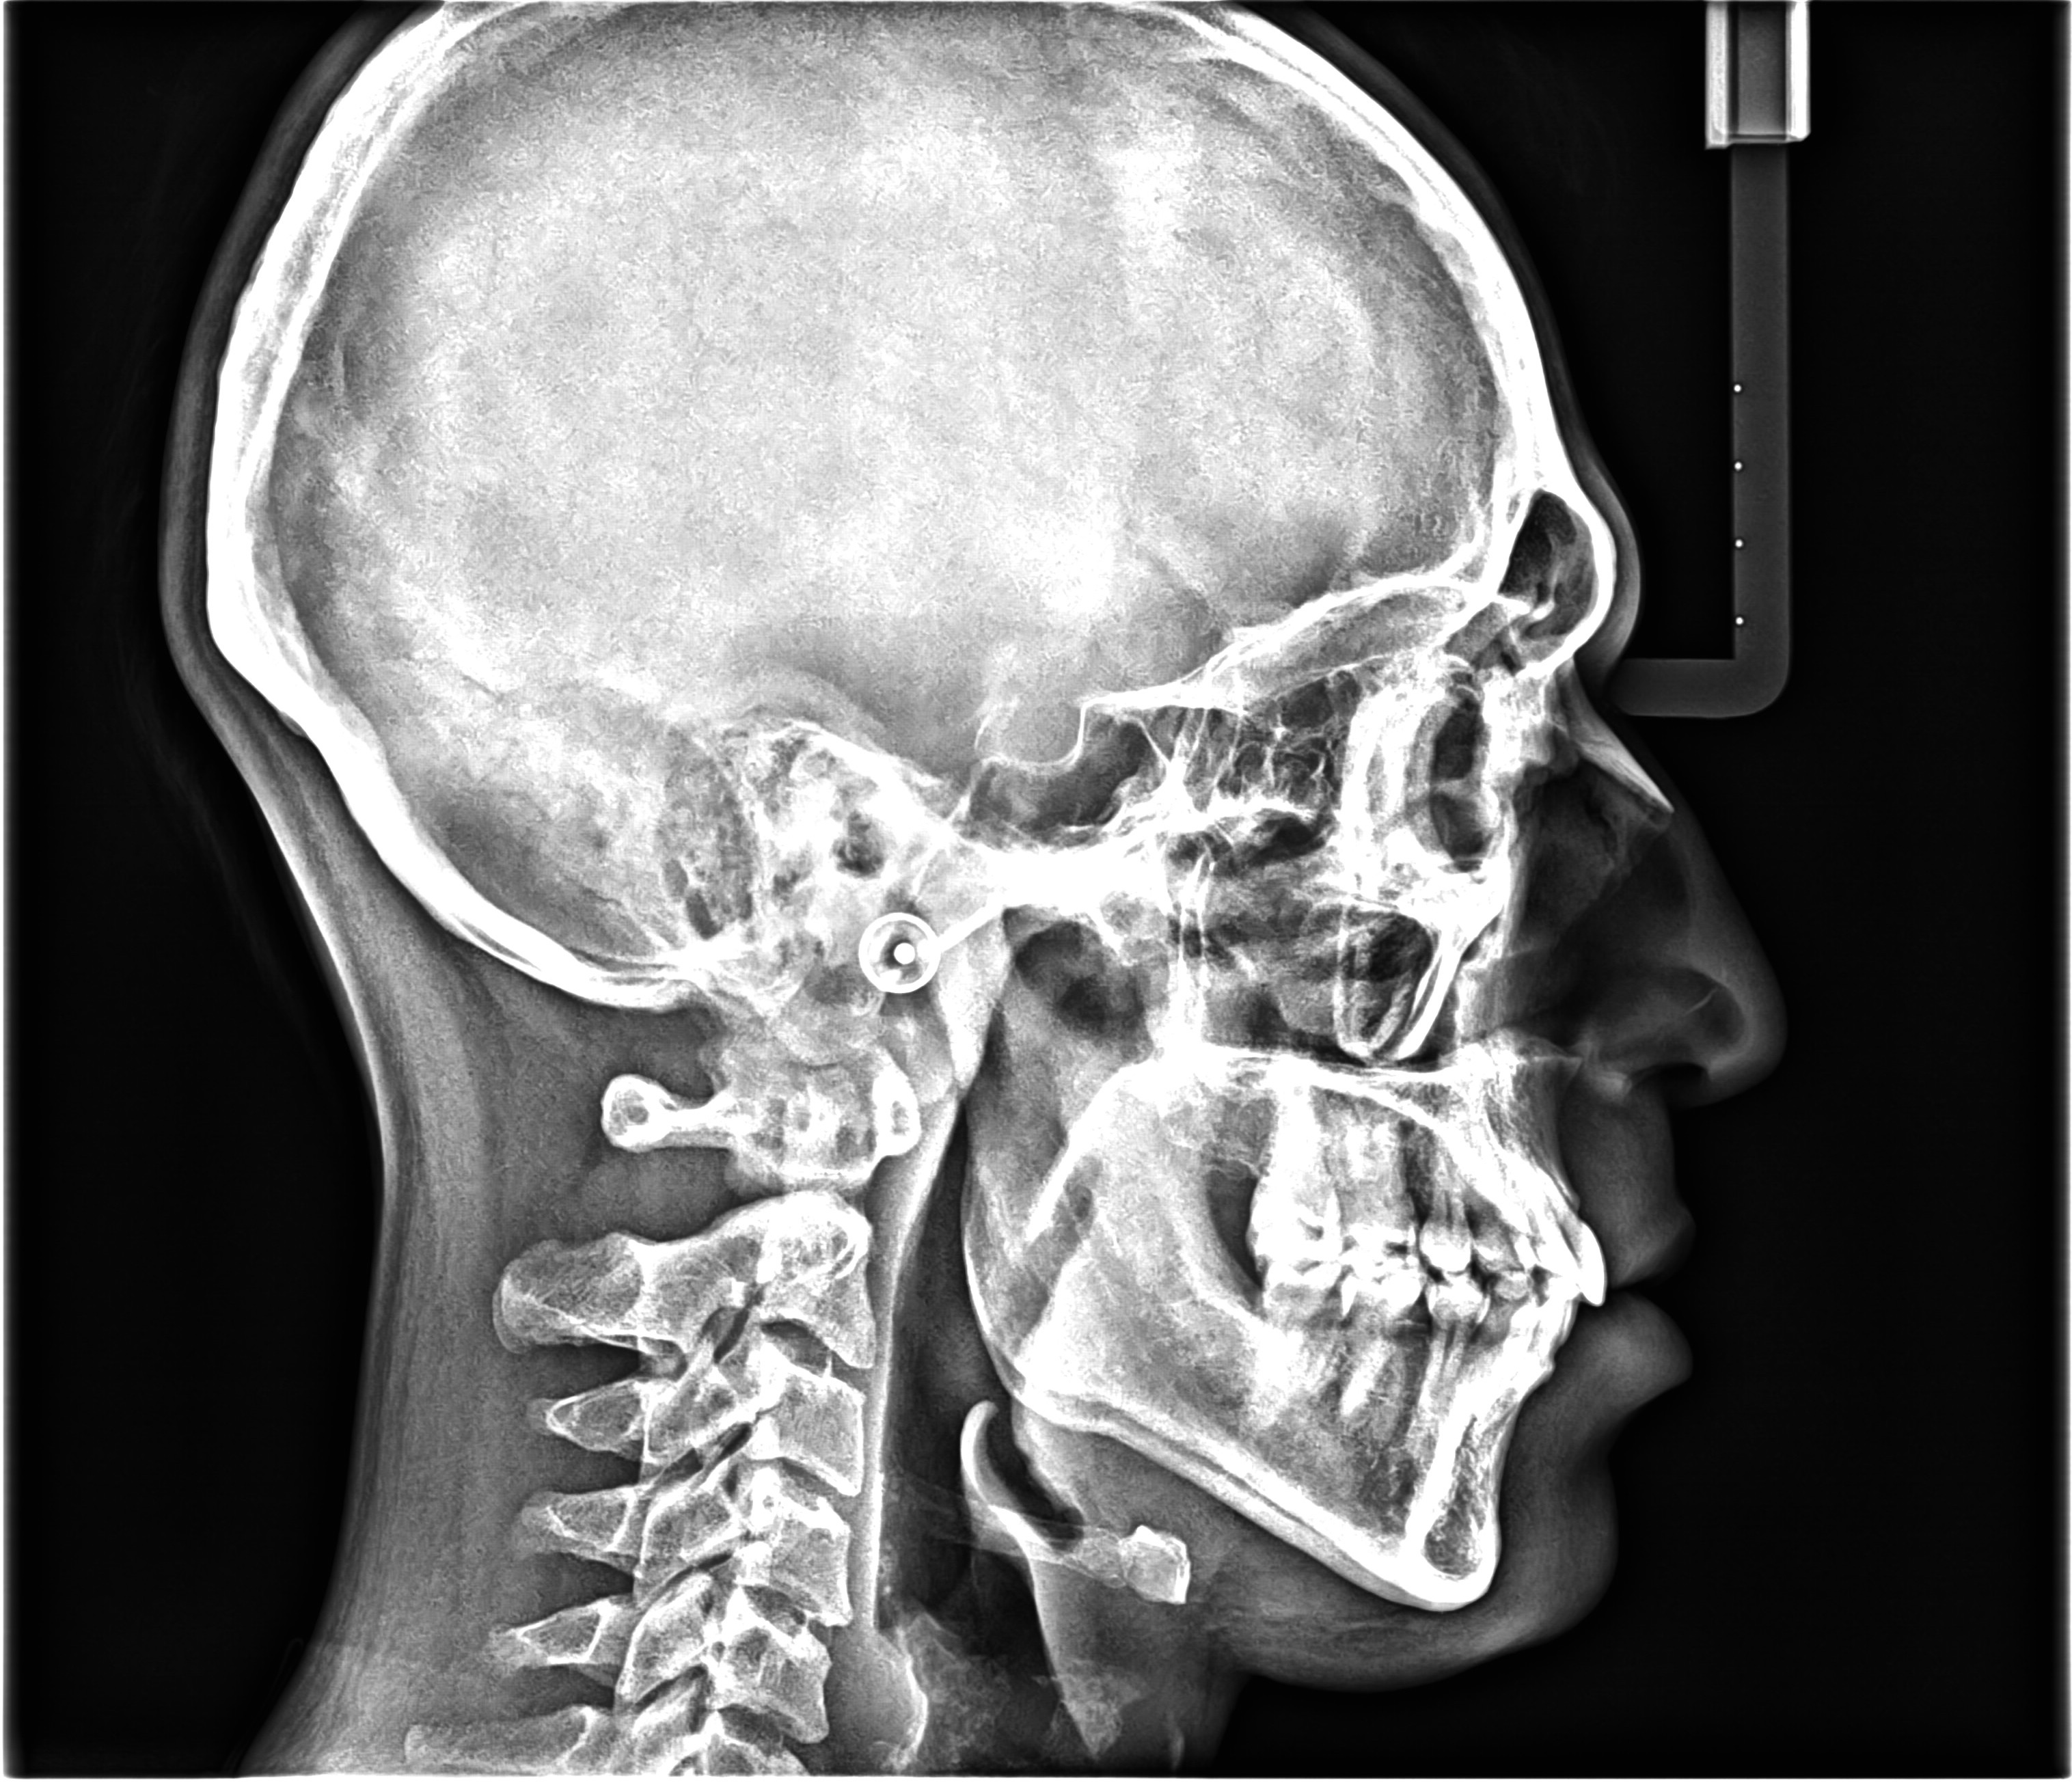

Cephalometric Analysis